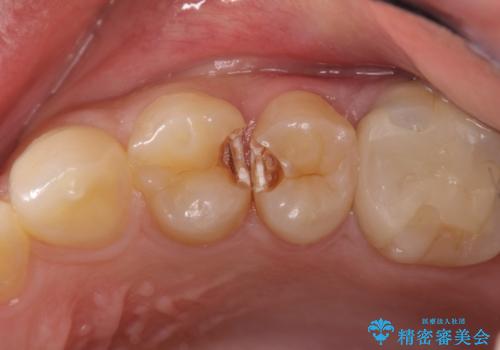

精密なむし歯の治療 セラミックインレー

- 定期健診にてむし歯を認めた患者さまです。

笑った時に見える部分だったためセラミックインレーにて修復しました。

保険治療で使える材料には制限があり、見た目だけでなく精度でも劣ります。当院でのセラミックインレーは歯とのつなぎ目を拡大鏡で確認して精度高く仕上げるため、むし歯のリスクを限りなく少なくできるよう治療します。